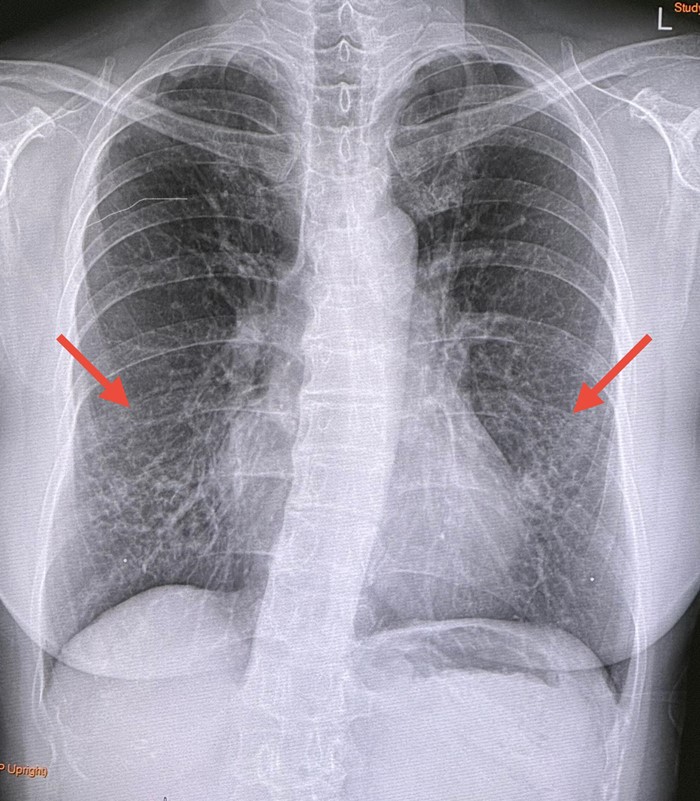

โพสต์ดังกล่าวระบุว่า ผู้ป่วยหญิงชาวไทย อายุ 63 ปี ไม่สูบบุหรี่ มีประวัติไอเรื้อรังนาน 8 ปี เป็นอาการไอแห้ง ๆ ไม่เหนื่อย เคยทำคอมพิวเตอร์สแกนปอดที่โรงพยาบาลอื่นเมื่อเดือนกุมภาพันธ์ 2567 พบหลอดลมโป่งพองในปอดทั้ง 2 ข้าง เก็บเสมหะเพาะเชื้อวัณโรคไม่ขึ้น

เมื่อปลายปีที่ผ่านมา ผู้ป่วยมีอาการไอปนเลือด แพทย์ที่โรงพยาบาลได้ส่องกล้องเข้าไปในหลอดลมเพื่อเก็บเสมหะเพาะเชื้อ พบเชื้อวัณโรคเทียมชื่อ Mycobacterium intracellulare ซึ่งไวต่อยา clarithromycin และ amikacin ผลตรวจเลือดค่าตับและไตปกติ แพทย์ได้เริ่มให้ยารักษา ได้แก่ rifampicin, ethambutol และ azithromycin รับประทานขนาดปกติทุกวัน ตั้งแต่วันที่ 21 มกราคม 2568

วินิจฉัย : โรคหลอดลมโป่งพอง ติดเชื้อวัณโรคเทียม M. intracellulare หลังรักษา 3 เดือน 20 วัน เกิดผลข้างเคียงทางตาจากยาอีแทมบูทอล (Ethambutol) คือเกิดประสาทตาอักเสบ (Optic neuritis) ทำให้การมองเห็นสีผิดปกติ (แยกสีน้ำเงินและเหลืองไม่ออก) ตามัว และมีภาพกลางจอมืด (central scotoma)